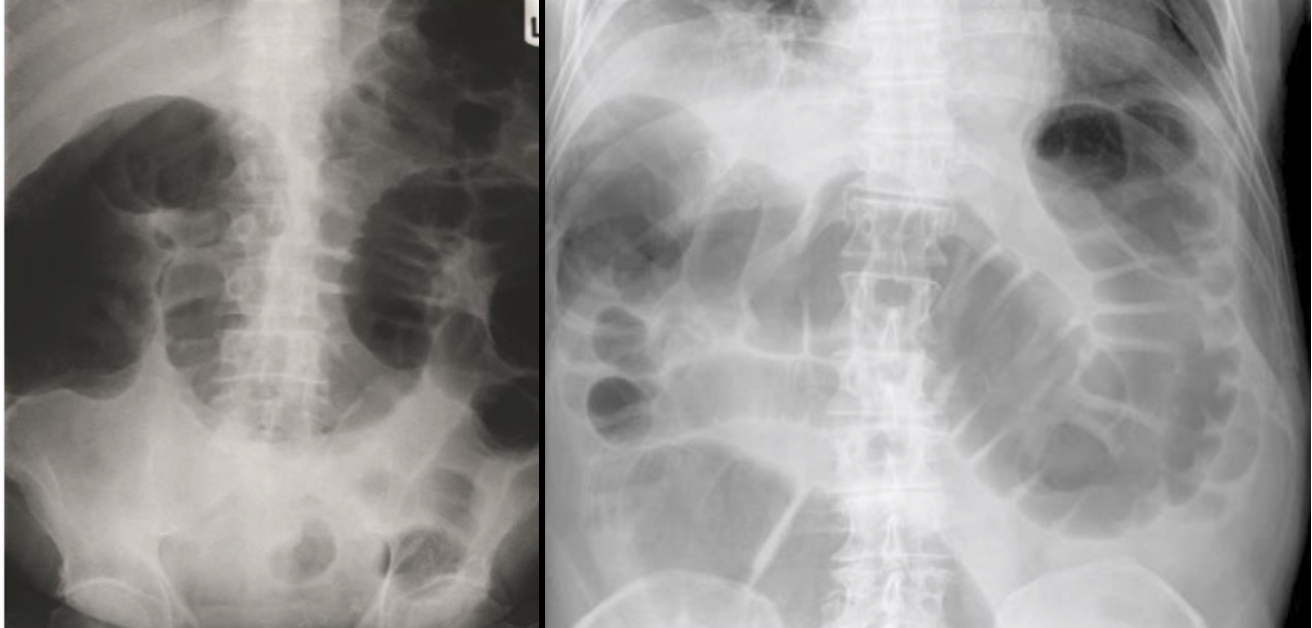

Radiology Imaging

• Plain radiography (flat and upright)

• Contrast radiography with enema

Computed tomography (CT) –

• This is the imaging modality of choice